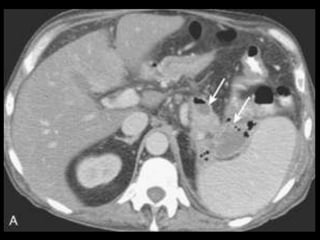

PANCREATITE AGUDA GRAVE

A administração de contraste IV é essencial,

especialmente em pacientes com PA grave, para

visualizar o pâncreas, diferenciar a glândula de

coleções líquidas adjacentes e do tecido

inflamatório peripancreático e demonstrar a

necrose pancreática.

Áreas focais ou difusas de realce diminuídas ou

ausente à TC contrastada dinâmica constituem

áreas de isquemia ou necrose.

TC tem precisão geral de 87% com S e E de 100%

para necrose extensa e 50% com áreas menores.

Coleções líquidas agudas

Ocorrem em cerca de 40% dos casos;

Podem ser em torno da glândula ou extra-

pancreático;

Carecem de cápsula e são confinadas ao espaço

anatômico onde se encontram;

Podem dissecar para outros locais: mediastino,

pararrenal posterior, órgãos sólidos ou parede de

alça intestinal.